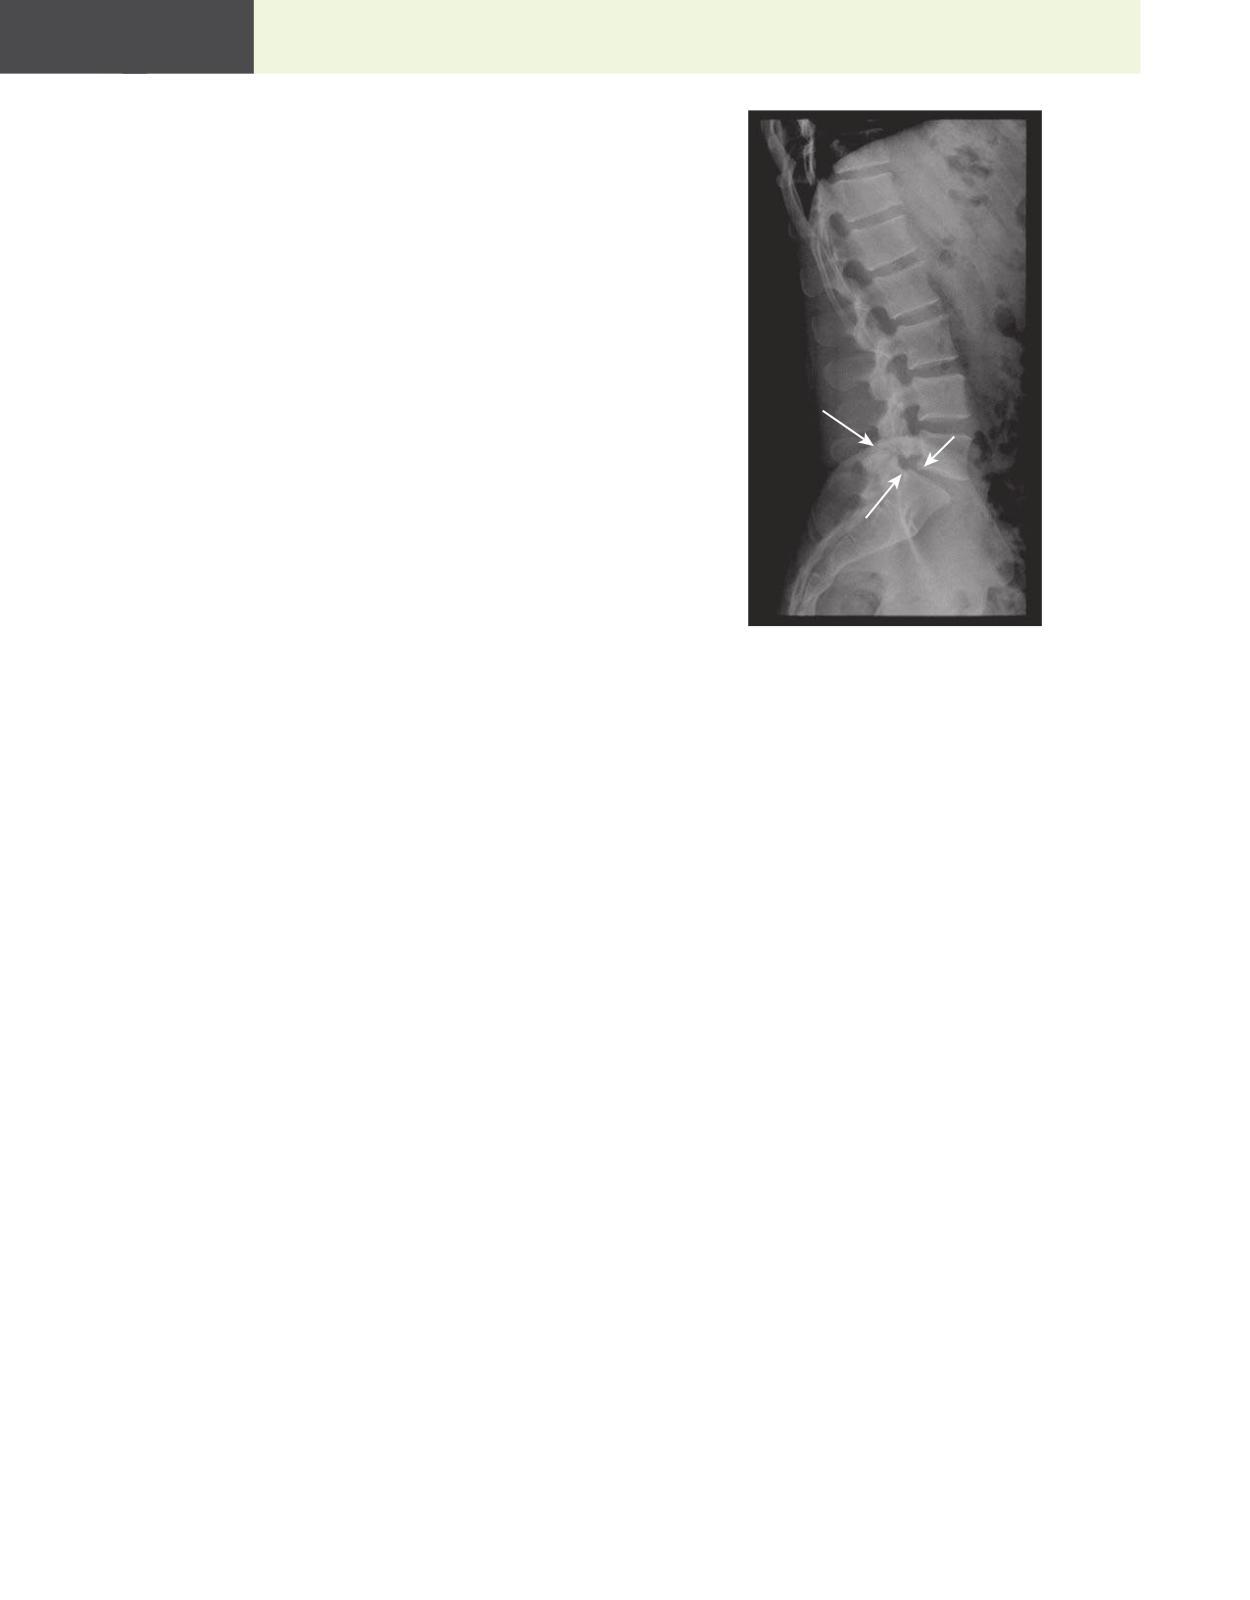

58. A 62-year-oī³d woman ī²s admī²tted to tī±e ī±ospī²taī³ because a 5-montī± ī±ī²story oī° back paī²n ī±as gotten progressī²veī³y worse. Sī±e ī°eeī³s reī³ī²eved wī±en sī±e bends ī°orward and worse wī±en sī±e waī³ks ī°or a ī°ew mī²nutes. Pī±ysī²caī³ examī²natī²on sī±ows sī±e ī±as 5/5 motor strengtī± bī²ī³ateraī³ī³y ī²n tī±e ī³ower extremī²tī²es. here ī²s

a sī³ī²gī±t sensatī²on deīcī²t on tī±e ī³eī°t medī²aī³ aspect oī° tī±e tī±ī²gī±. An x-ray oī° tī±e spī²ne sī±ows tī±e L4 vertebraī³ body ī±as sī³ī²pped anterī²orī³y, wī²tī± ī°racture oī° tī±e zygapopī±ysī²aī³ joī²nt (Fī²g 1.2) Wī±ī²cī± oī° tī±e ī°oī³ī³owī²ng ī²s tī±e most ī³ī²keī³y dī²agnosī²s?

A. Spondyī³oī³ysī²s and spondyī³oī³ī²stī±esī²s